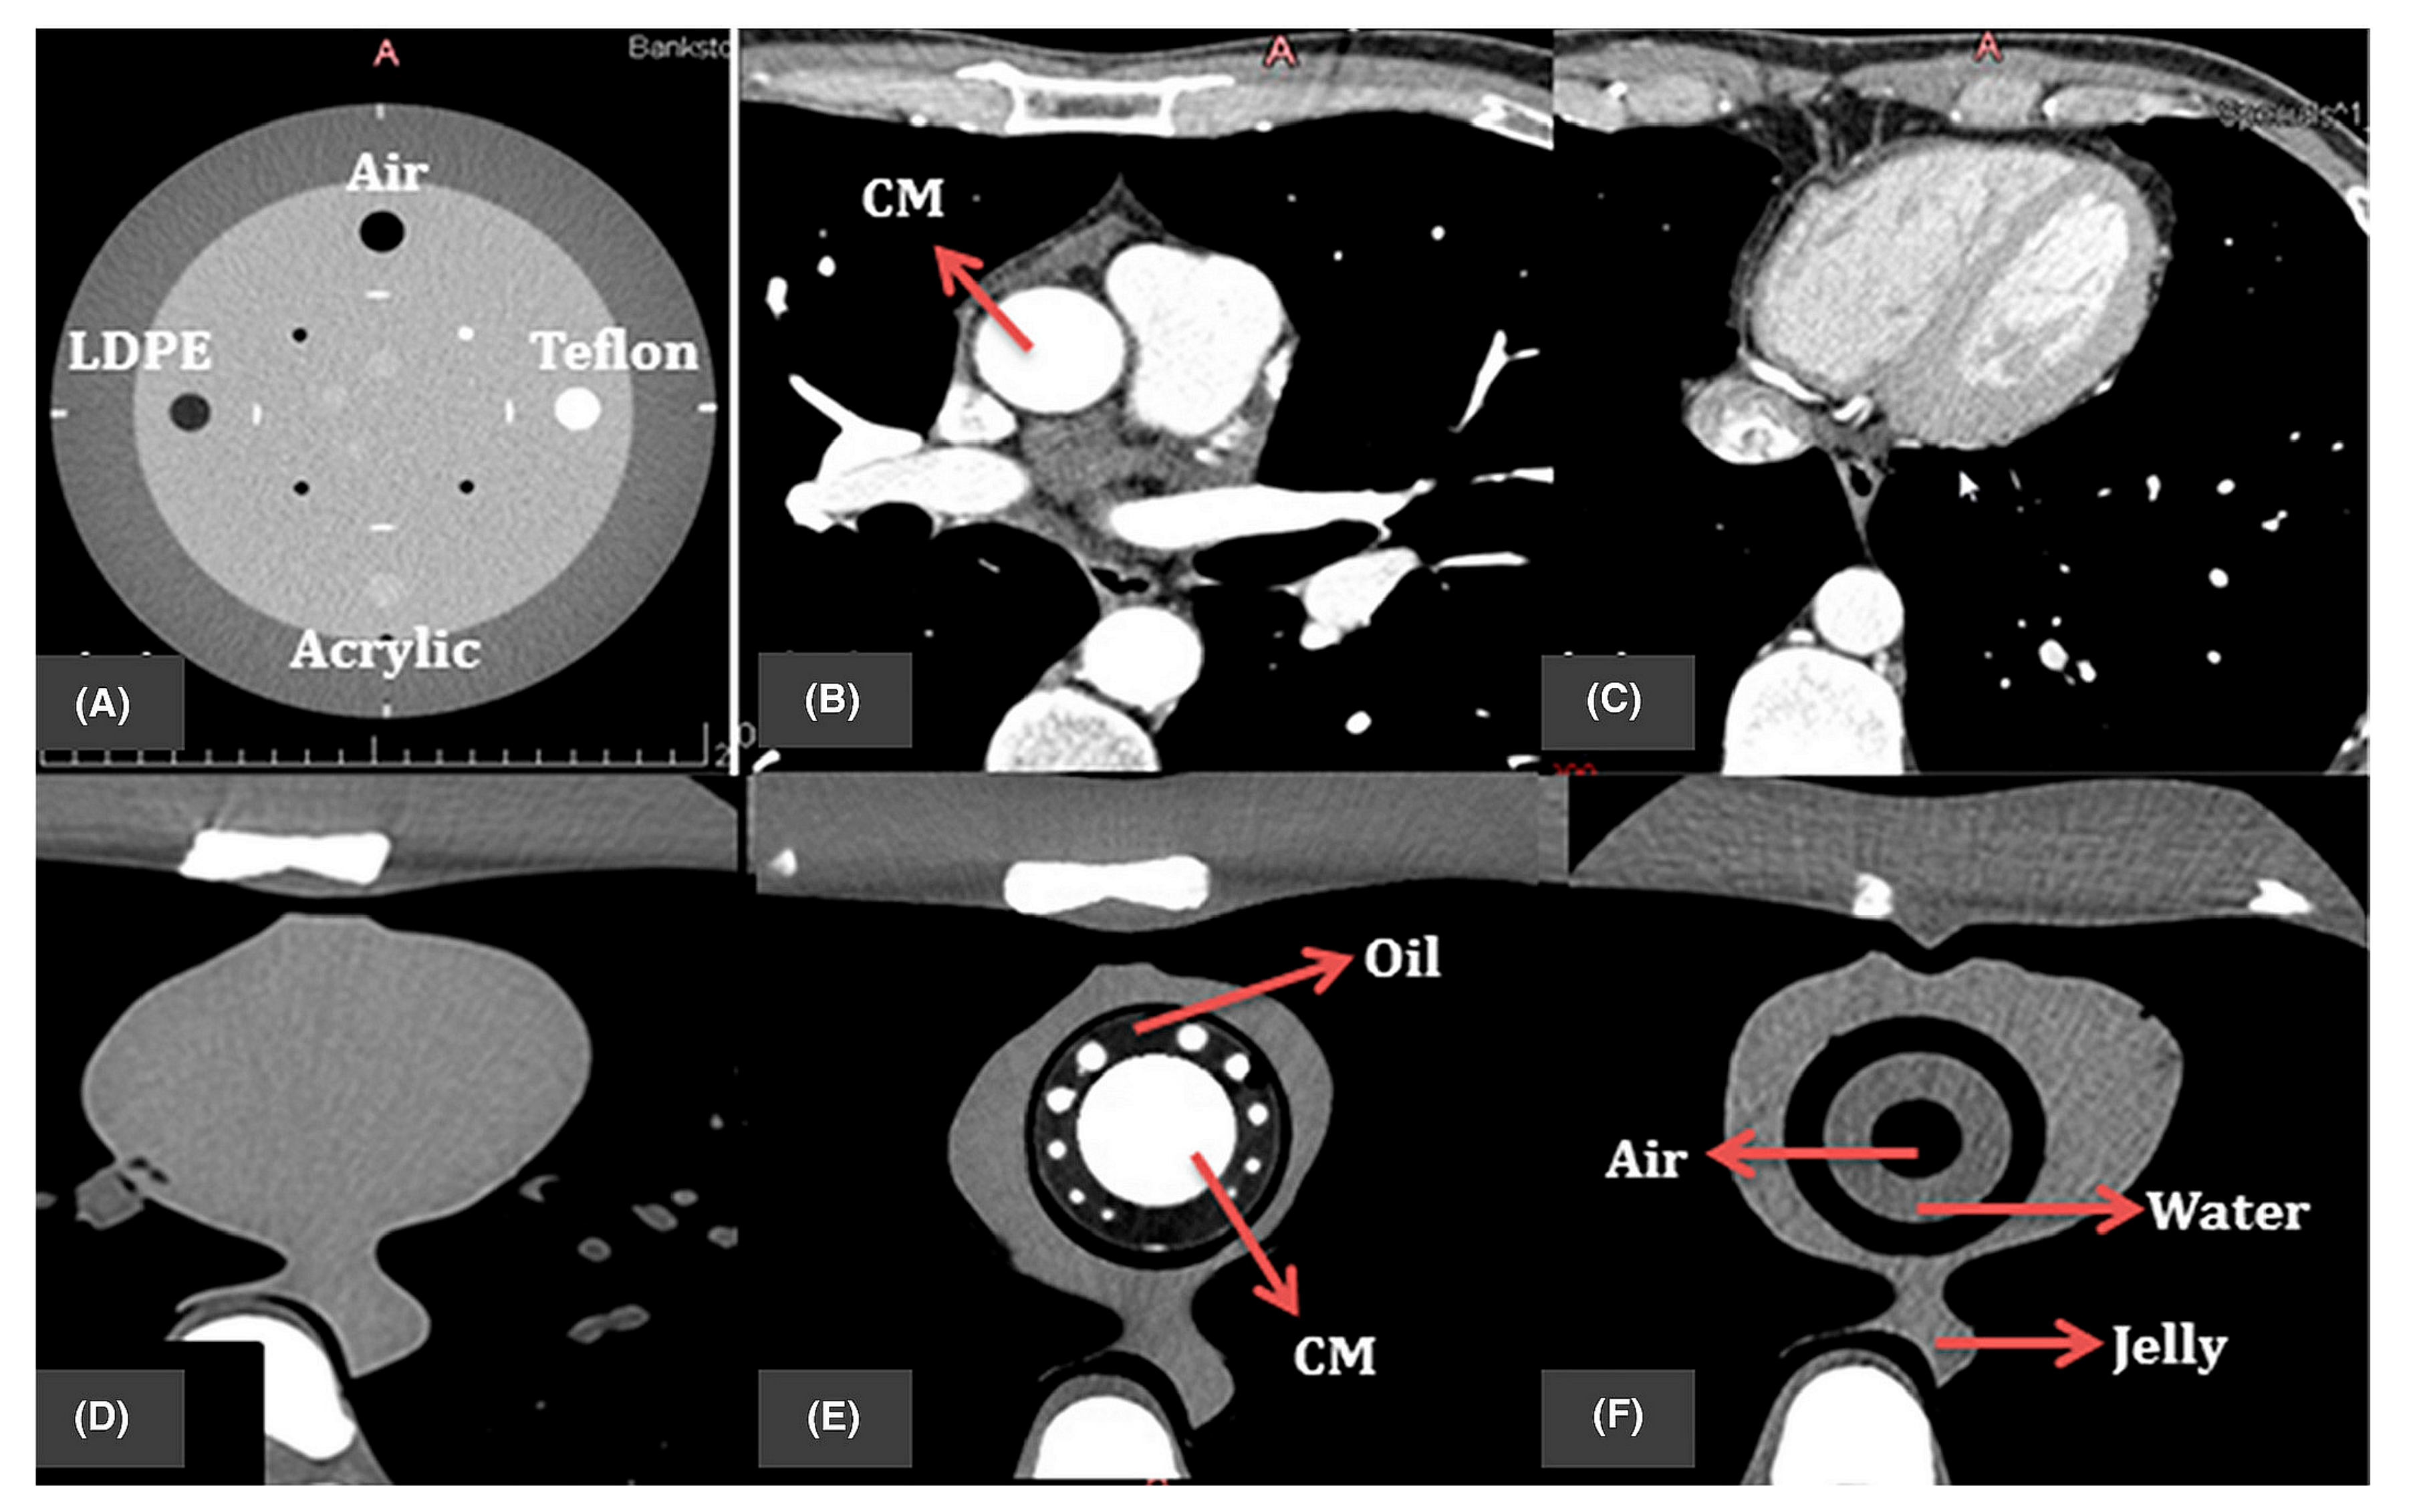

- Wu, C.-A.; Squelch, A.; Sun, Z. Investigation of Three-dimensional Printing Materials for Printing Aorta Model Replicating Type B Aortic Dissection. Curr. Med. Imaging Rev. 2021, 17, 843–849. [Google Scholar] [CrossRef]

- Sun, Z.; Ng, C.K.C.; Wong, Y.H.; Yeong, C.H. 3D-Printed Coronary Plaques to Simulate High Calcification in the Coronary Arteries for Investigation of Blooming Artifacts. Biomolecules 2021, 11, 1307. [Google Scholar] [CrossRef]

- Sun, Z.; Ng, C.K.C.; Squelch, A. Synchrotron radiation computed tomography assessment of calcified plaques and coronary stenosis with different slice thicknesses and beam energies on 3D printed coronary models. Quant. Imaging Med. Surg. 2019, 9, 6–22. [Google Scholar] [CrossRef] [PubMed]

- Sun, Z. 3D printed coronary models offer new opportunities for developing optimal coronary CT angiography protocols in imaging coronary stents. Quant. Imaging Med. Surg. 2019, 9, 1350–1355. [Google Scholar] [CrossRef]

- Wu, C.-A.; Squelch, A.; Sun, Z. Assessment of optimization of computed tomography angiography protocols for follow-up type B aortic dissection patients by using a 3D-printed model. J. 3D Print. Med. 2022, 6, 117–127. [Google Scholar] [CrossRef]

- Aldosari, S.; Jansen, S.; Sun, Z. Optimization of computed tomography pulmonary angiography protocols using 3D printed model with simulation of pulmonary embolism. Quant. Imaging Med. Surg. 2019, 9, 53–62. [Google Scholar] [CrossRef]

- Aldosari, S.; Jansen, S.; Sun, Z. Patient-specific 3D printed pulmonary artery model with simulation of peripheral pulmonary embolism for developing optimal computed tomography pulmonary angiography protocols. Quant. Imaging Med. Surg. 2019, 9, 75–85. [Google Scholar] [CrossRef] [PubMed]

- Abdullah, K.A.; McEntee, M.F.; Reed, W.; Kench, P.L. Development of an organ-specific insert phantom generated using a 3D printer for investigations of cardiac computed tomography protocols. J. Med. Radiat. Sci. 2018, 65, 175–183. [Google Scholar] [CrossRef]

- Mørup, S.D.; Stowe, J.; Precht, H.; Gervig, M.H.; Foley, S. Design of a 3D printed coronary artery model for CT optimization. Radiography 2022, 28, 426–432. [Google Scholar] [CrossRef]